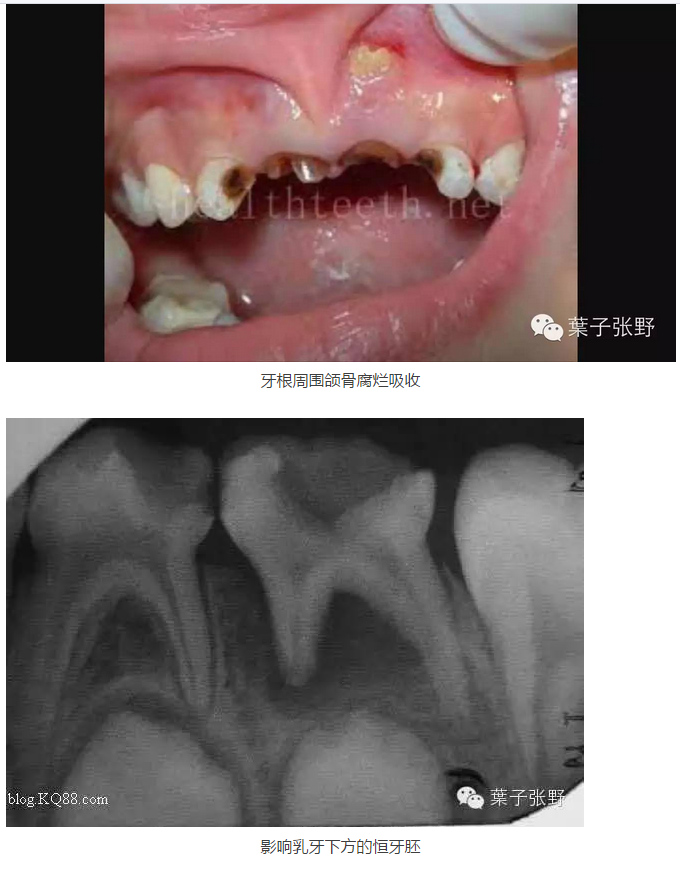

好多家長認為乳牙反正要換,蛀牙不需要治療,等換牙就好了,真的是換牙就好了嘛?不治療會有什么危害呢?

讓我用圖片和短句說明吧。